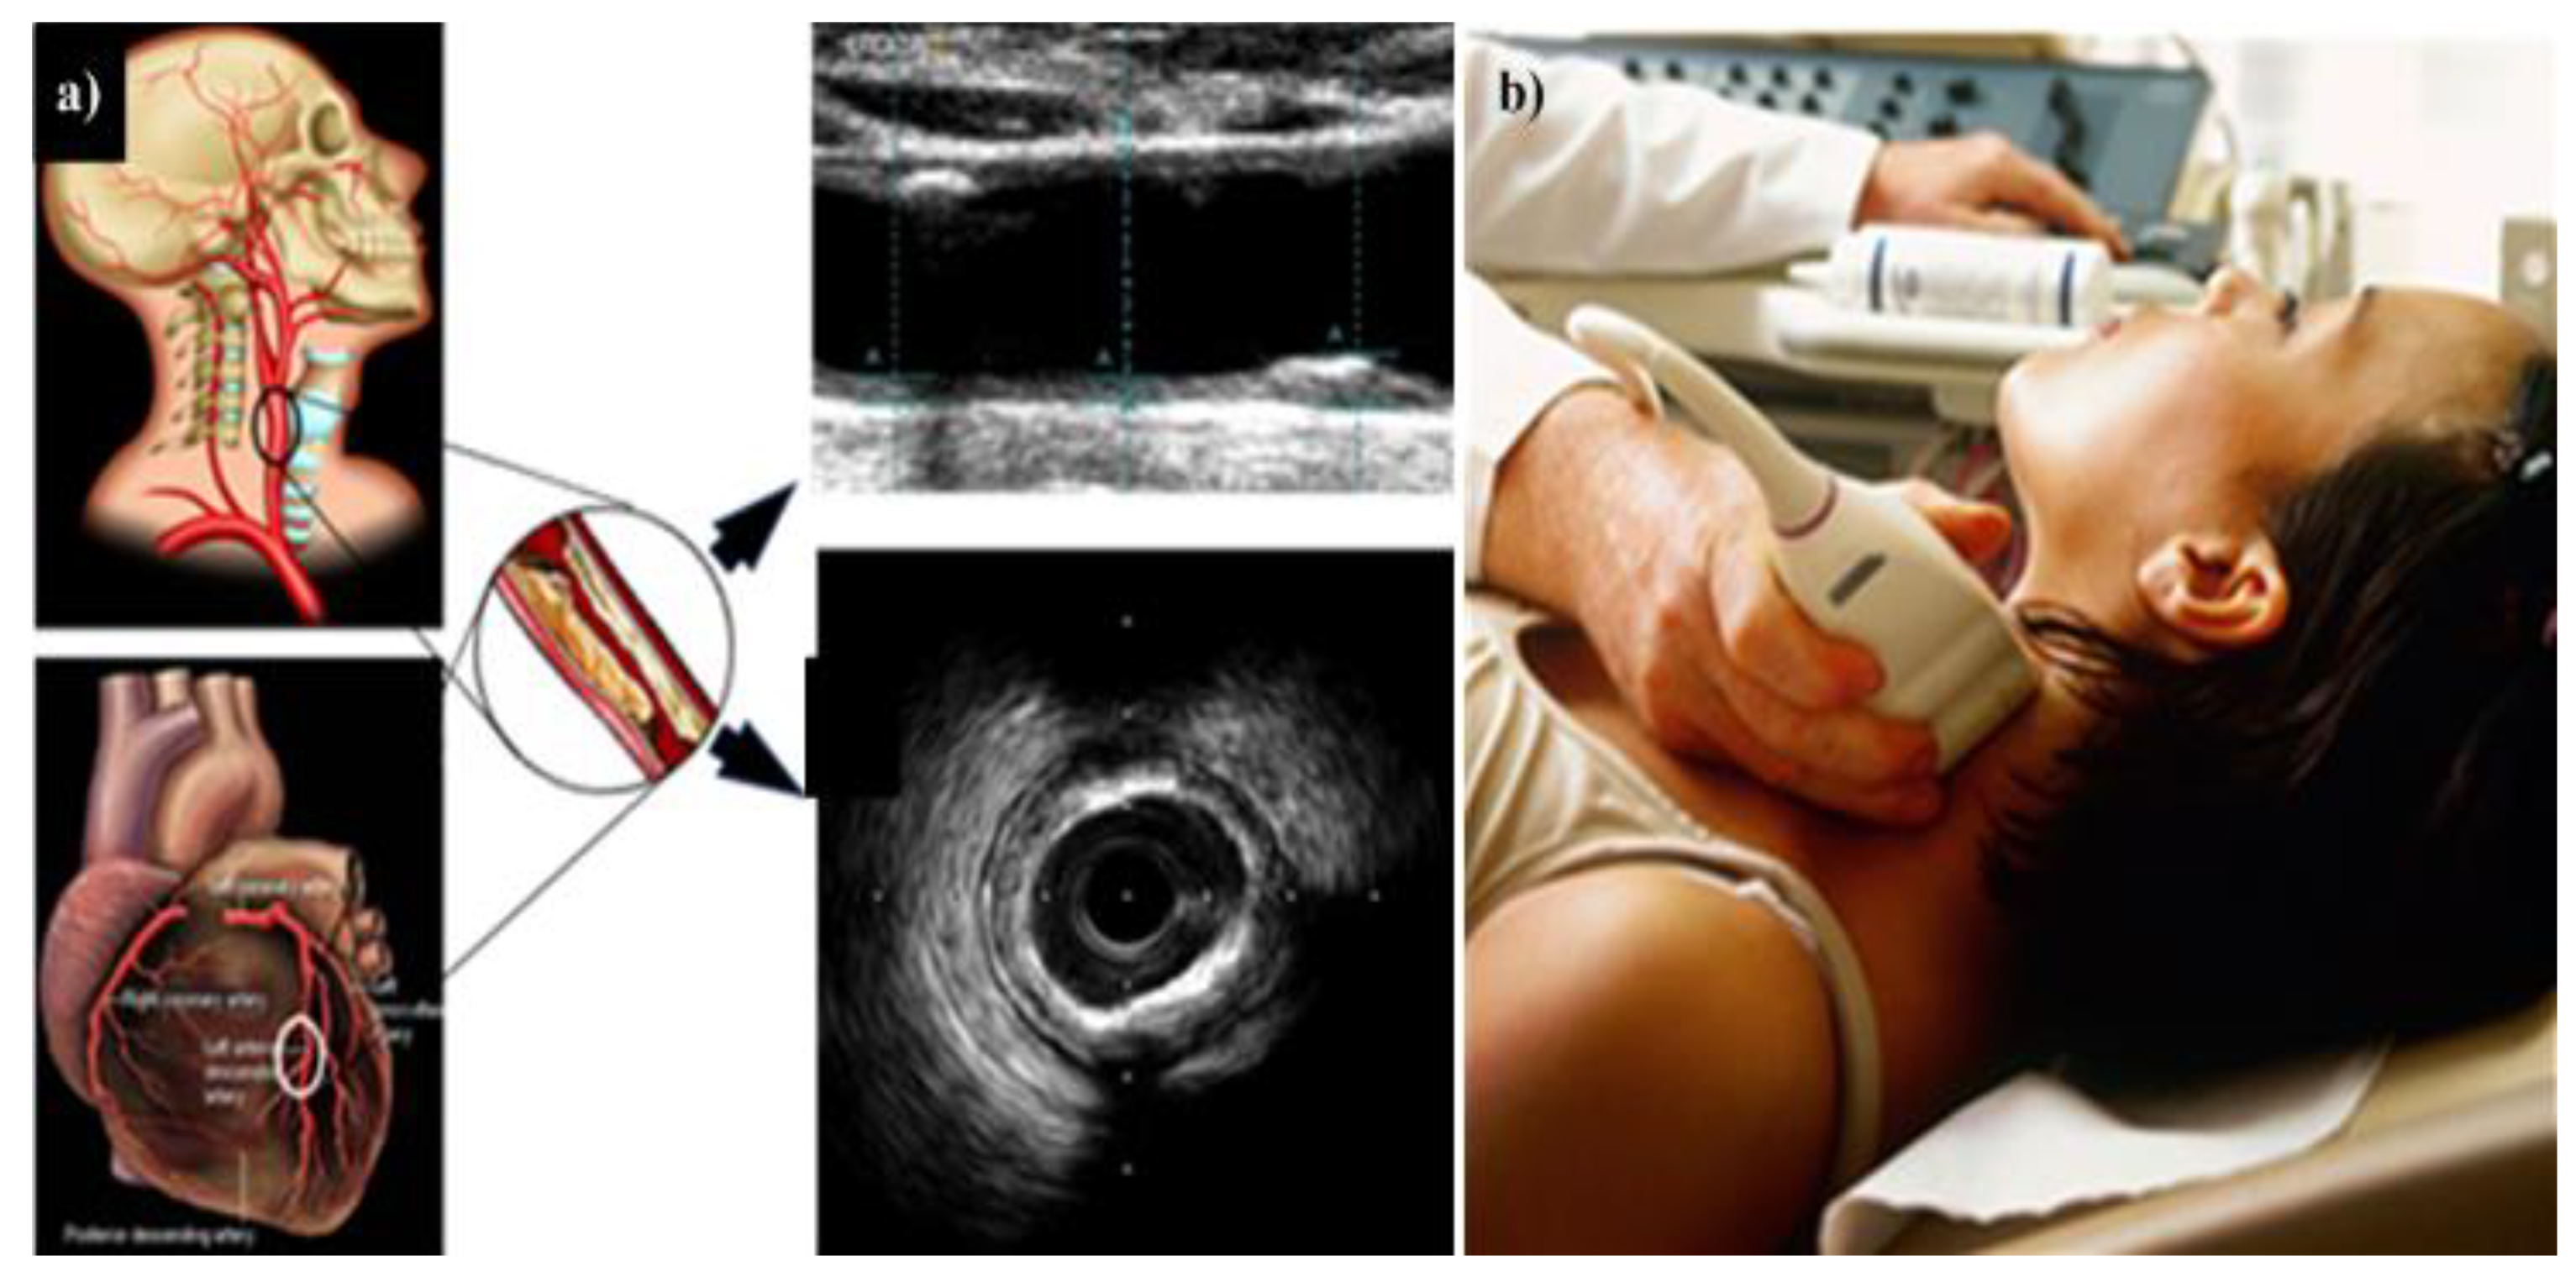

4. Carotid Imaging for CVD Risk Assessment in DR Patients

4.1. DR and Cerebrovascular/Carotid Artery Disease

4.2. Carotid Artery Disease—A Surrogate of Coronary Artery Disease or Cardiovascular Disease